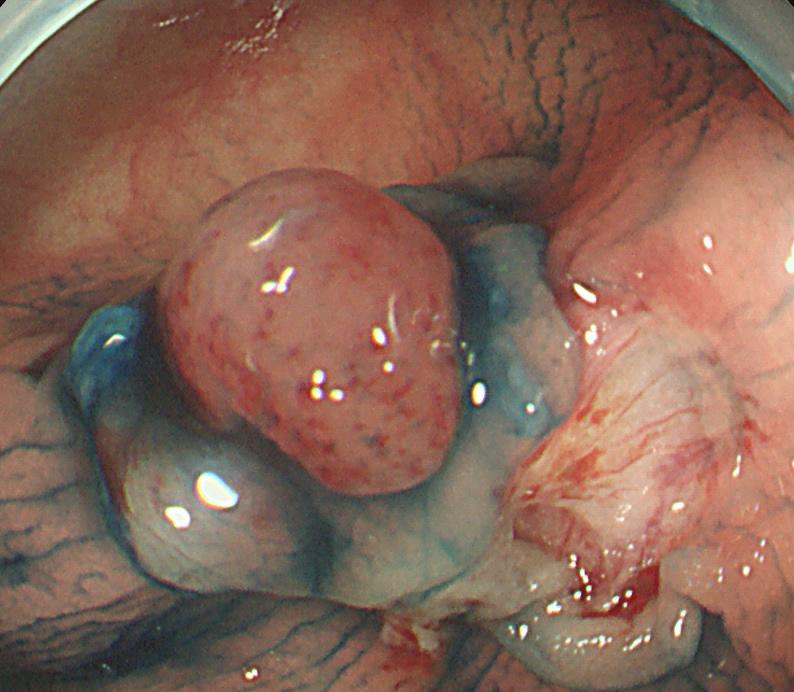

実際の「Extended Cold法」の模様を紹介します

しかしながら・・・いつも、このような綺麗な「目玉焼き」ができる訳ではありません。実際はスネアー(ワイヤー)が、うまくかからずに「分断」「分割」になったり、カンシ(ジャンボ・バイオプシー)を併用することも多いです。

患者さんの立場で言うなら、「ポリープ切除後の写真」をしっかり確認することが最も重要です。

重要なのはポリープではなく右の写真!!!